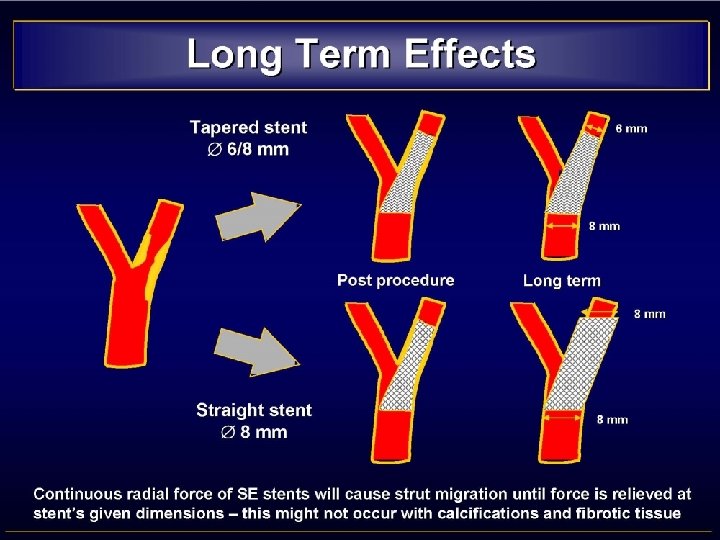

• MISMATCH CCA-ICA